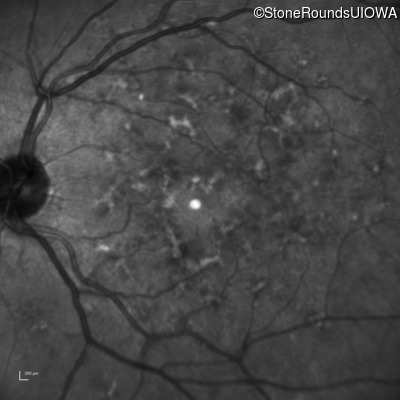

Infrared Fundus Photograph - Right - 20/25 +2

Exemplar